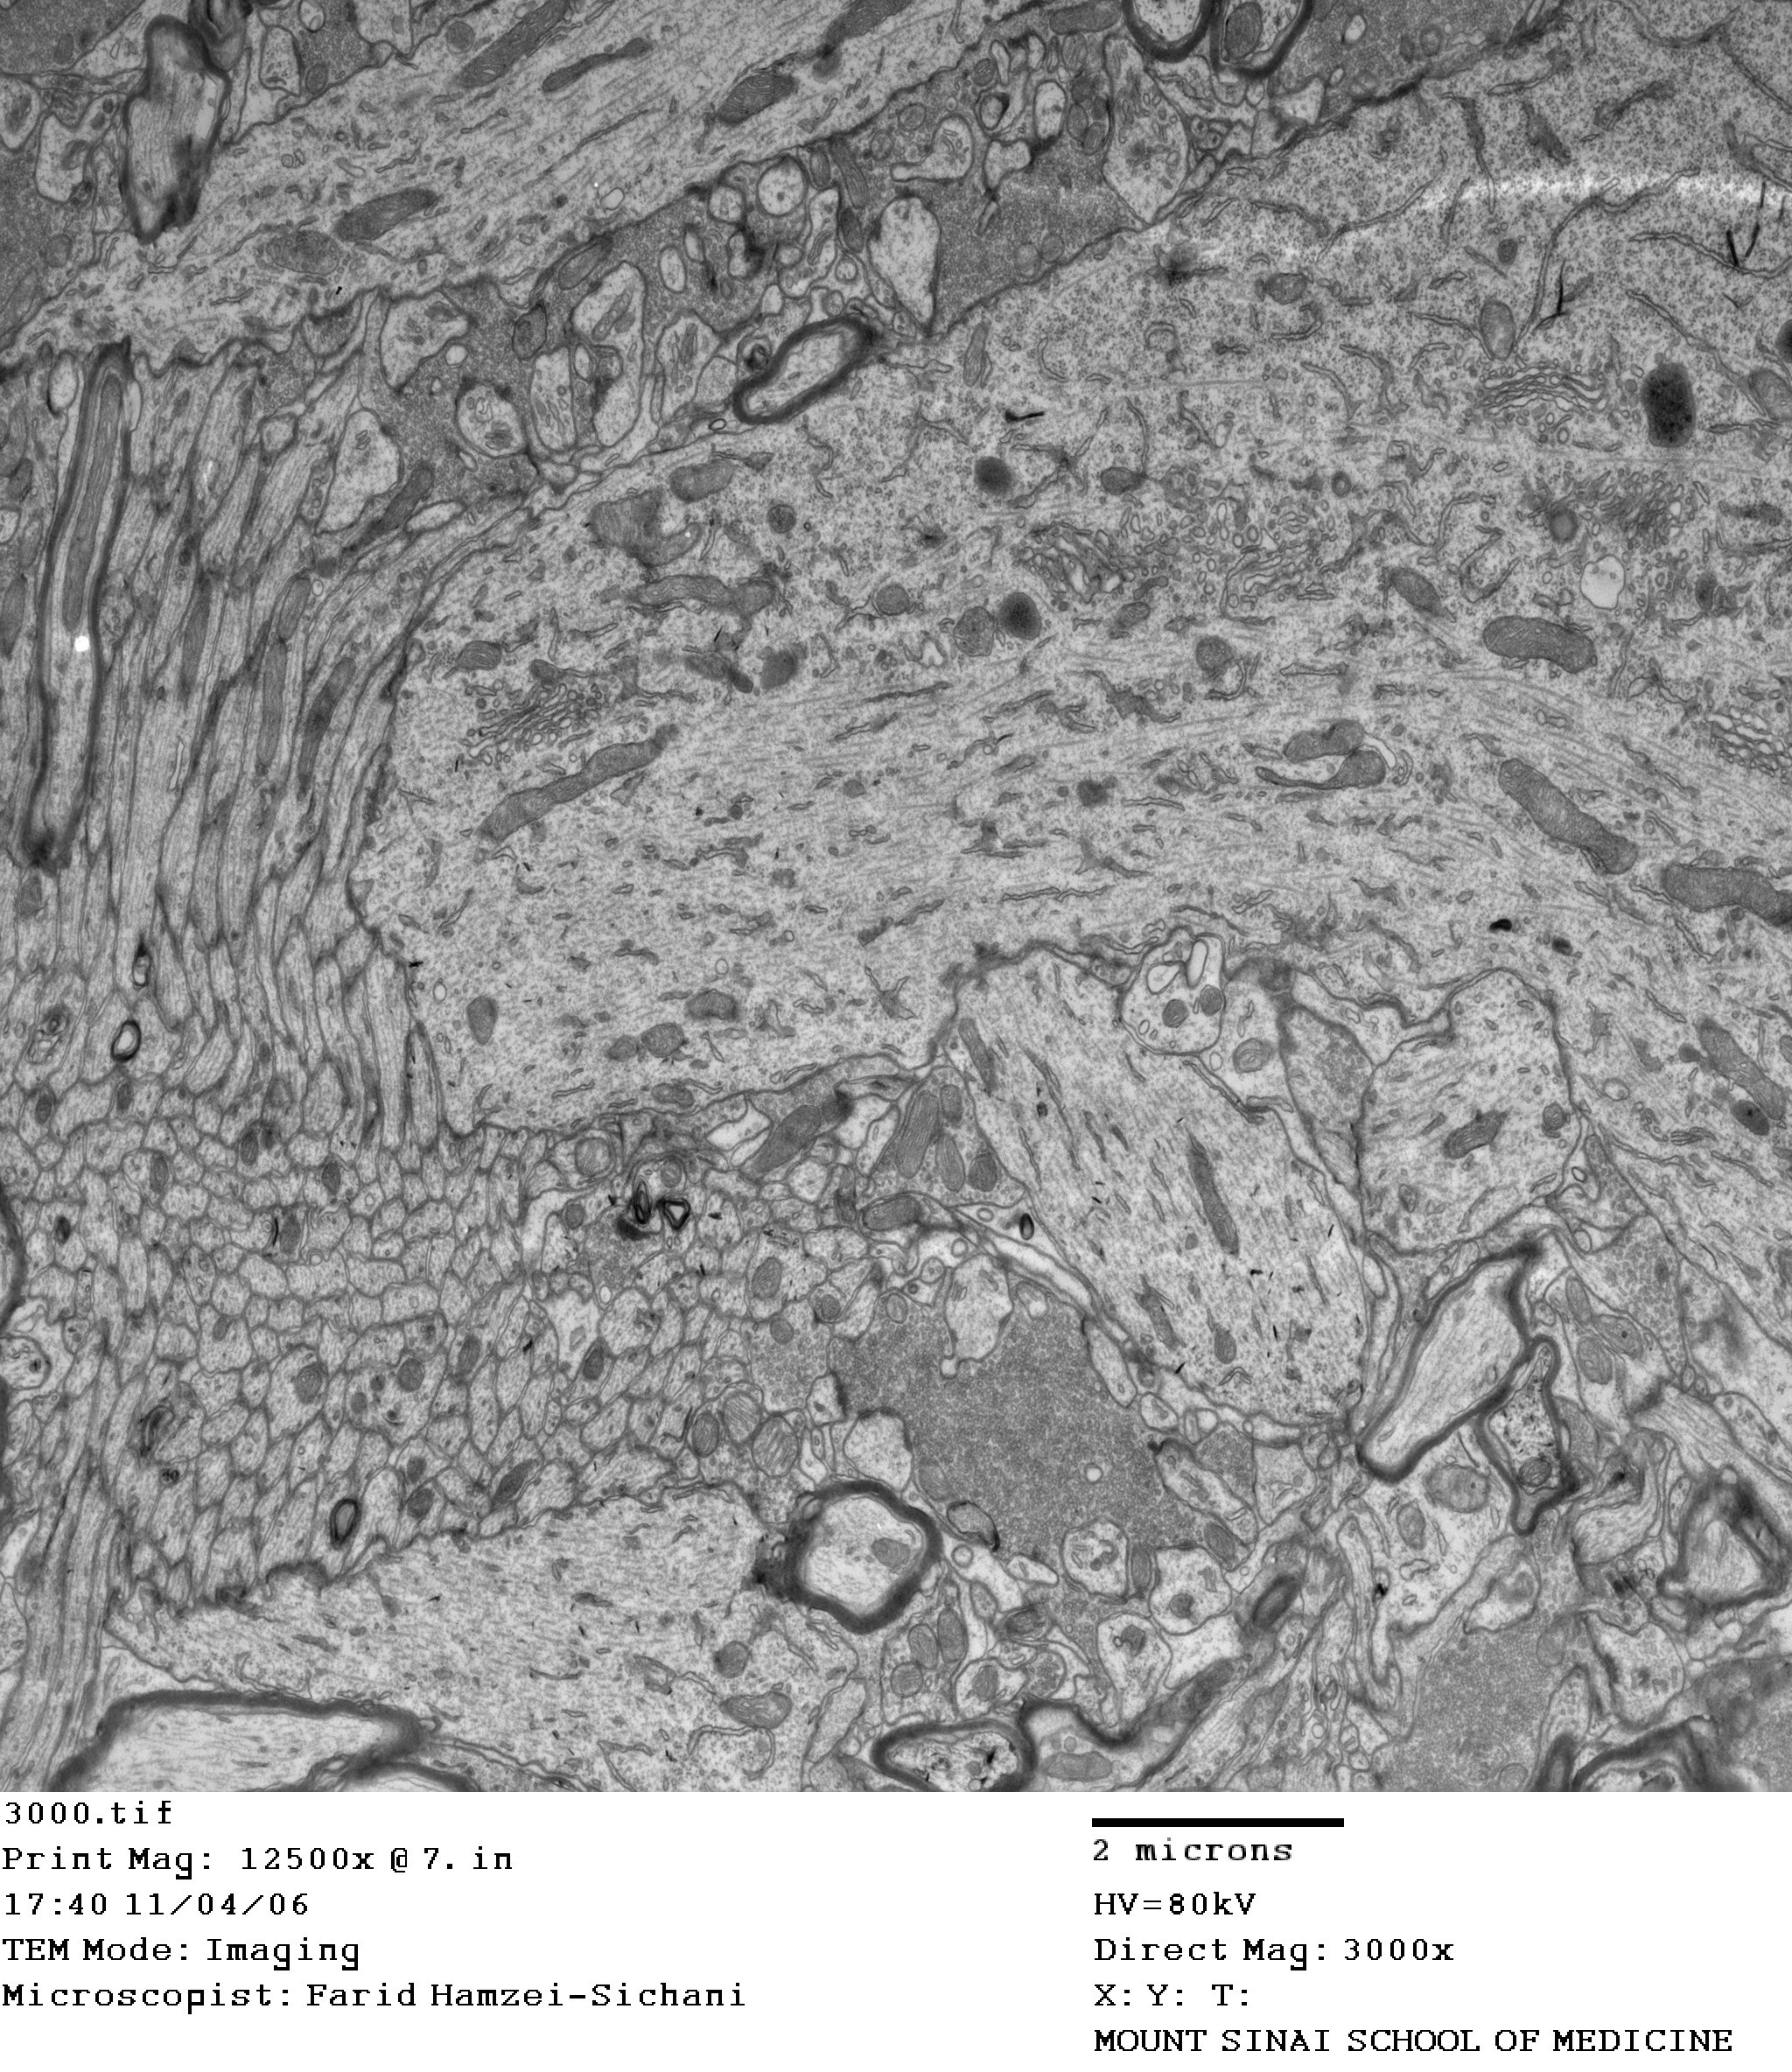

Ultrastructural substrates of high frequency cortical oscillations

other EM images

Mixed synapses